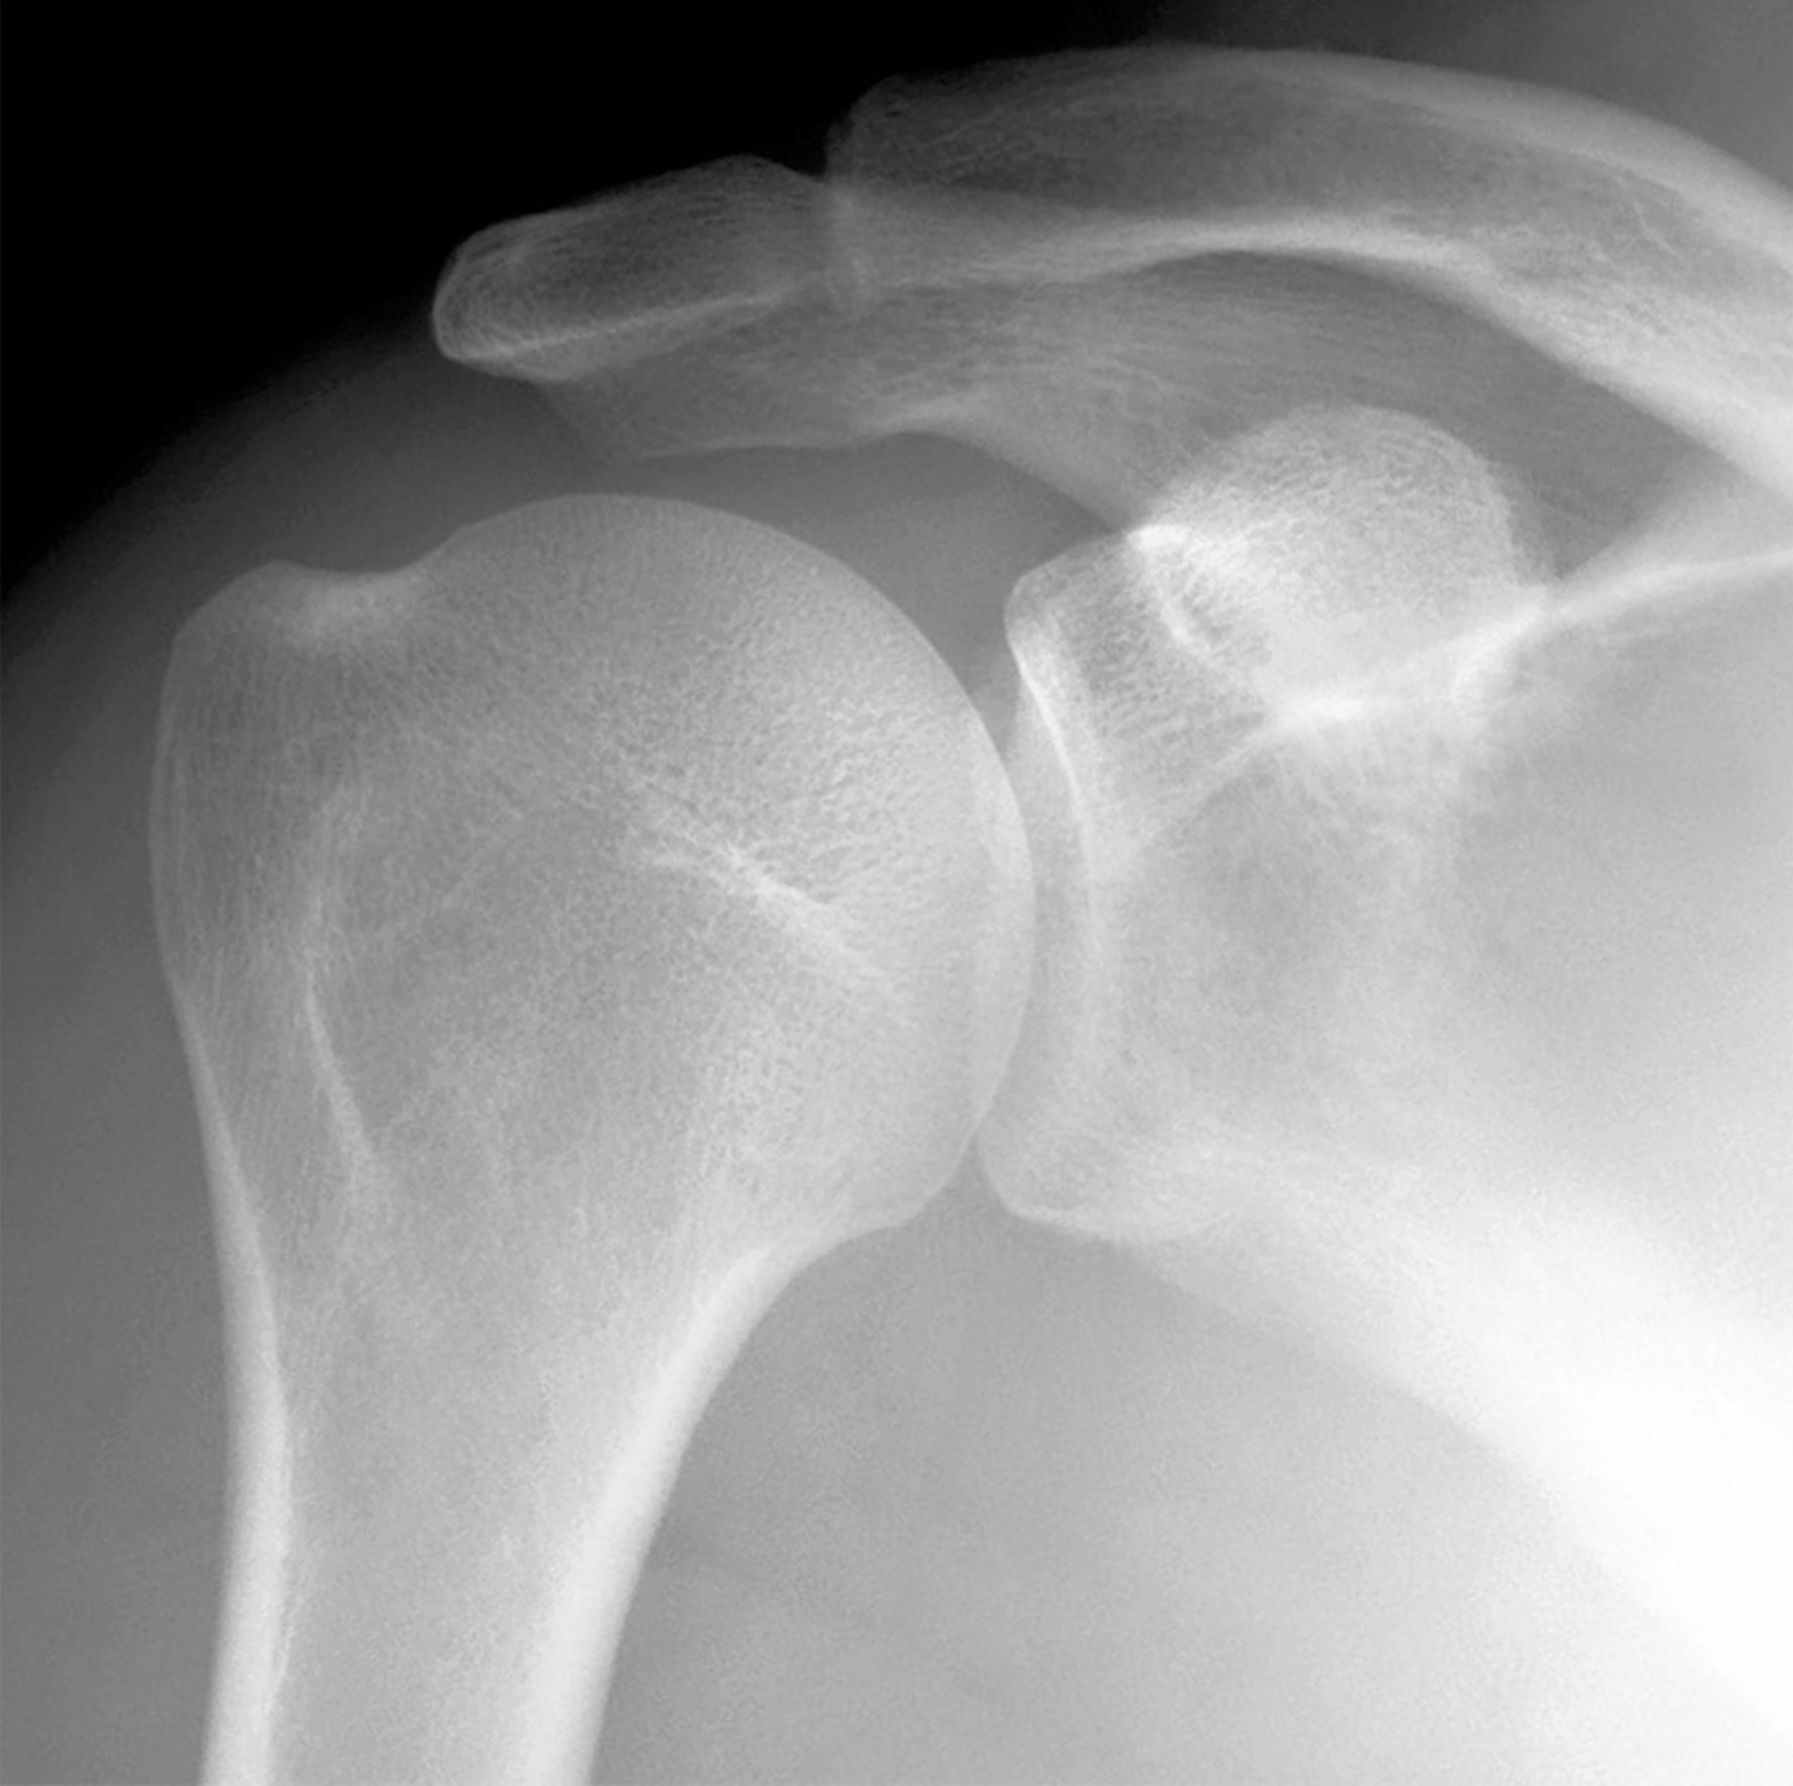

Lecture 29: Shoulder and Elbow Joints - Separation, Dislocation, Rotator Cuff Tear, Tommy John - M. Johnson

1. A shoulder separation and a shoulder dislocation occur at different joints. Review the anatomy of the acromioclavicular joint. Include bones, articulations, ligaments, capsules, cavities, movements and limitations of movement, and relationships.

2. The shoulder joint has extreme mobility paired with inherent instability. Review the anatomy of the glenohumeral joint. Include bones, articulations, ligaments, capsules, cavities, contents, muscles, movements and limitations of movements, vasculature, lymphatic drainage, innervation, and relationships.

True/False. 1 Point Each.

1. The clavicle is suspended from above by the trapezius and sternocleidomastoid muscles. Thus, a downward blow to the lateral margin of the acromion might rupture the acromioclavicular, trapezoid, and conoid ligaments resulting in a shoulder separation. (True)

2. An increase in joint mobility is paired with a decrease in joint stability. (True)

3. The conoid ligament is medial to the trapezoid ligament and lateral to the superior transverse scapular ligament. (True)

4. The "empty can" (oil can) test demonstrated by Dr. Bollard tests for either supraspinatus tendon tear (rotator cuff tear) or injury to the suprascapular nerve. (True)

5. The subacromial bursa does not normally communicate with the glenohumeral synovial joint cavity except in the case of a rotator cuff tear involving the supraspinatus muscle. (True)

6. The synovial sheath for the tendon of origin of the long head of the biceps within the bicipital groove is a diverticulum of the glenohumeral synovial joint cavity. (True)

7. A rupture of the tendon of origin for the long head of the biceps often injures the glenoid labrum. (True)

8. The glenohumeral joint capsule is relatively lax at the inferior margin. Thus, the initial movement of a shoulder dislocation tends to be downward. (True)

9. The glenohumeral ligaments are internal thickenings of the anterior wall of the glenohumeral joint capsule. (True)

10. Impingement of the shoulder joint commonly occurs between the greater tubercle and the coracoacromial arch. (True)